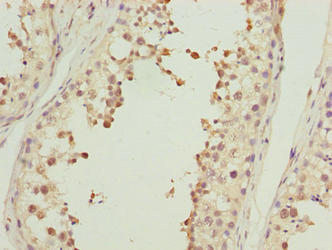

Immunohistochemistry of paraffin-embedded human testis tissue using CSB-PA897577LA01HU at dilution of 1:100

Immunohistochemistry of paraffin-embedded human prostate cancer using CSB-PA897577LA01HU at dilution of 1:100